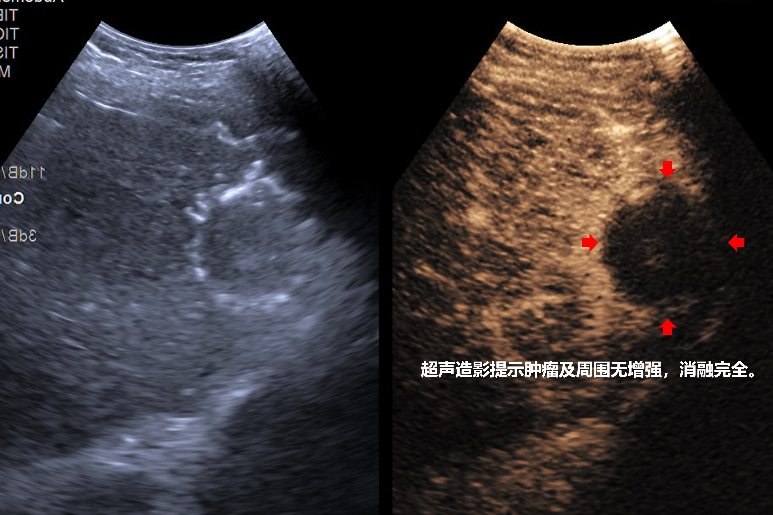

手术当日,麻醉与围术期医学科率先发力,为患者实施全身麻醉并通过呼吸机精准调控呼吸,为手术创造了稳定的操作条件。超声介入科团队在交大二附院姜珏教授的技术指导下,凭借丰富的临床经验与精准的操作技巧,在超声引导下注入人工腹水,成功将肿瘤与膈肌隔离保护,随后将消融针精准置入肿瘤周边及中心位置,通过热消融技术将肿瘤组织彻底“灭活”。消融操作完成后,普外一科团队开展腹腔镜下全面探查,对术区进行精细止血处理,确保手术无并发症风险。整个手术过程衔接紧密、安全顺利,术后患者状态良好。经术后超声造影评估,肿瘤被完整灭活,瘤周安全边界消融充分,治疗效果达到预期。